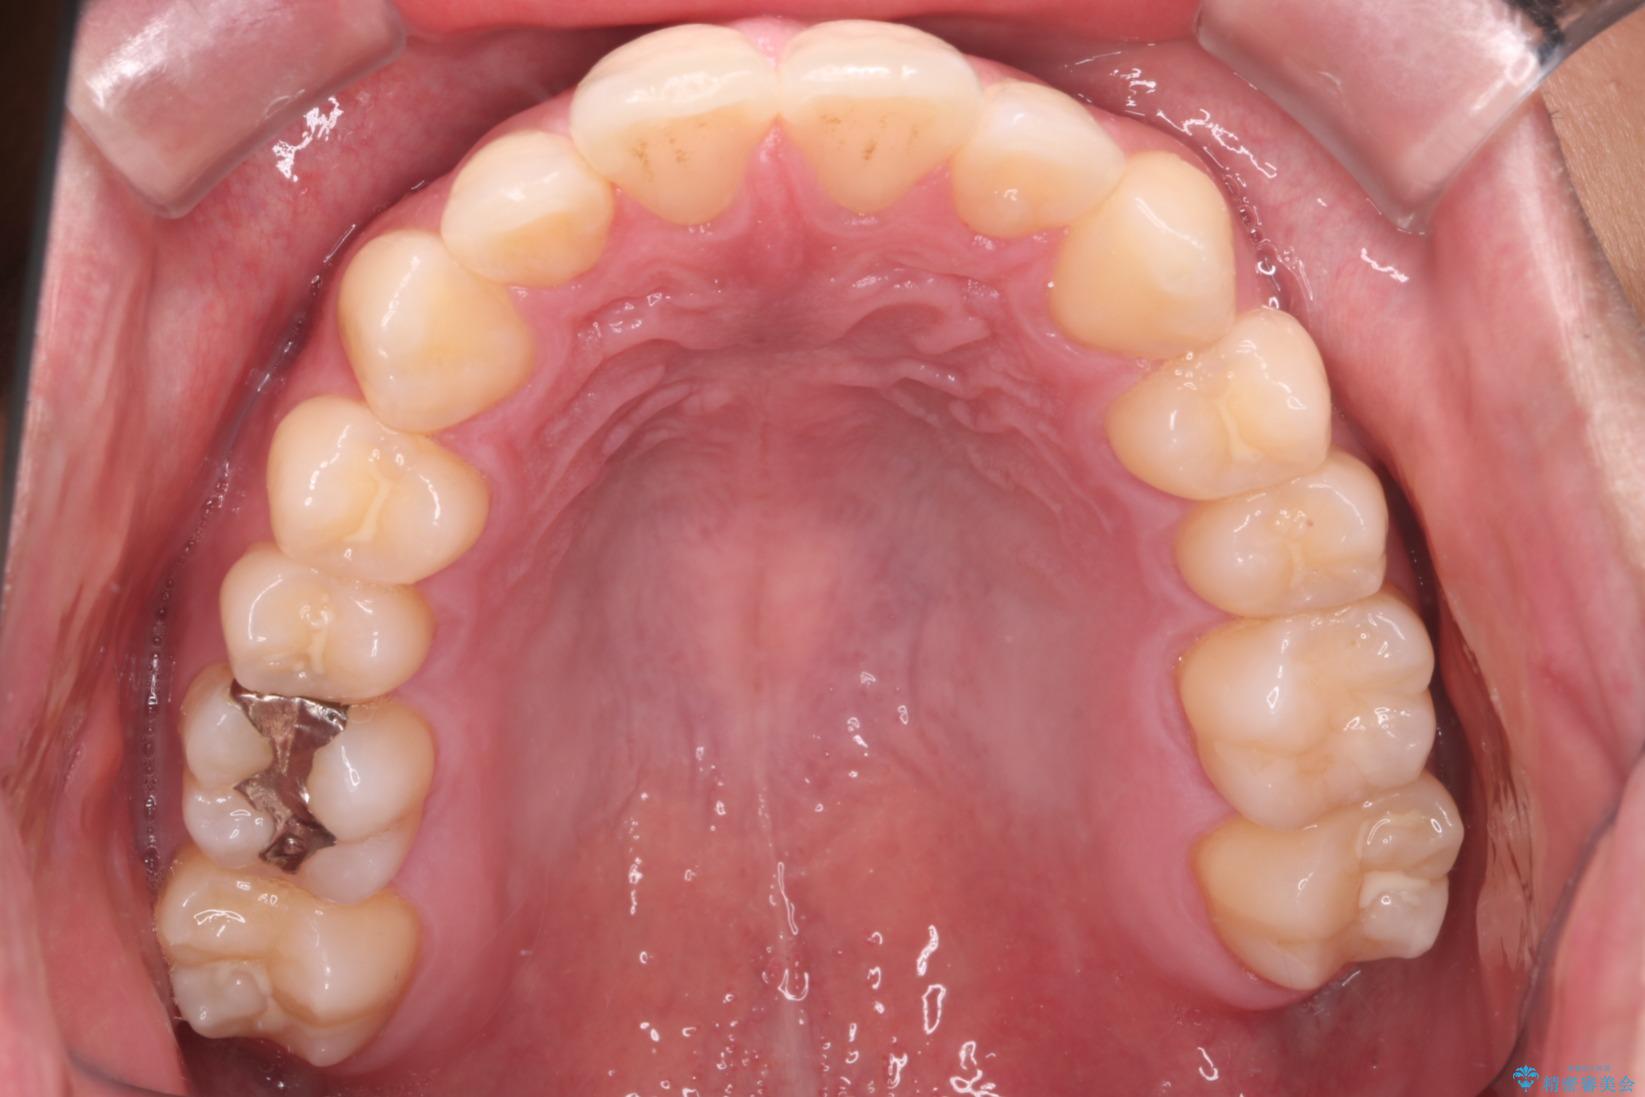

治療計画

インビザラインでの治療を希望されました。

IPR(歯と歯の間を削る処置)を行うことで、前歯の位置とがたつき整える治療計画を立てました。